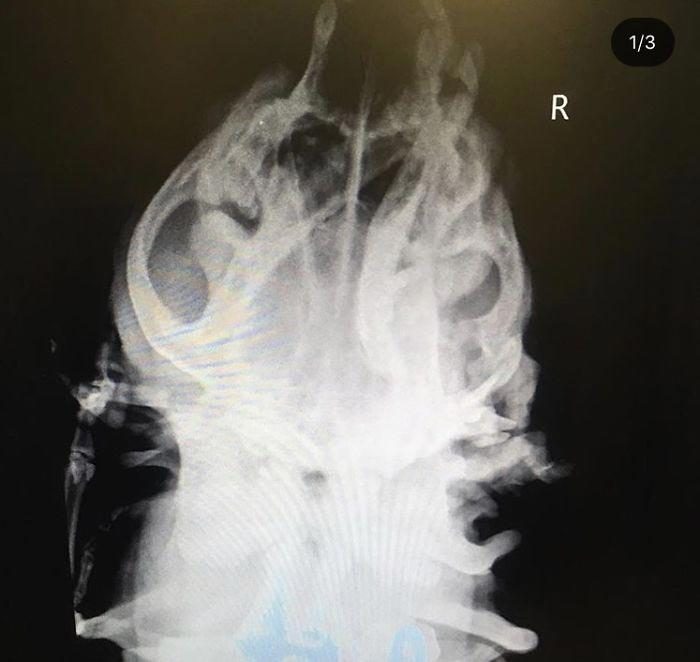

На первом рентгеновском снимке видно, как сложен череп собаки

У нее есть дополнительная орбитальная кость вокруг глазницы, вероятно, от черепа близнеца, которого она поглотила в утробе, что делает ее череп более выпуклым. Красный круг показывает два набора костей подъязычной кости. Желтый показывает, что позвонки не прикреплены так, как должны быть.